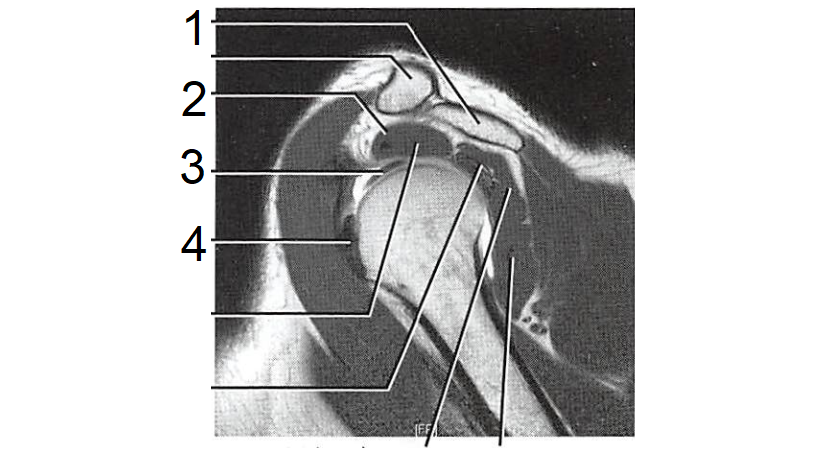

8

1 - Acrômio

2 - M. supraespinhal

3 - Tendão do M. bíceps braquial

4 - Tendão do M. subescapular